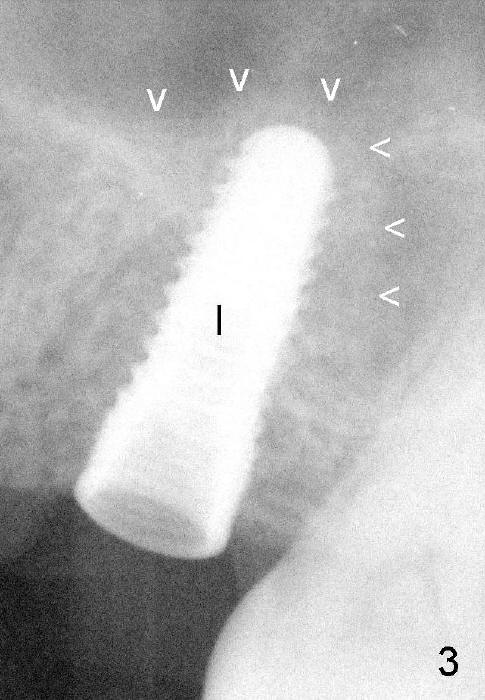

Fig.3: A 4.5x12 mm bone-level implant (I) is placed with dome-shaped bone graft (arrowheads).